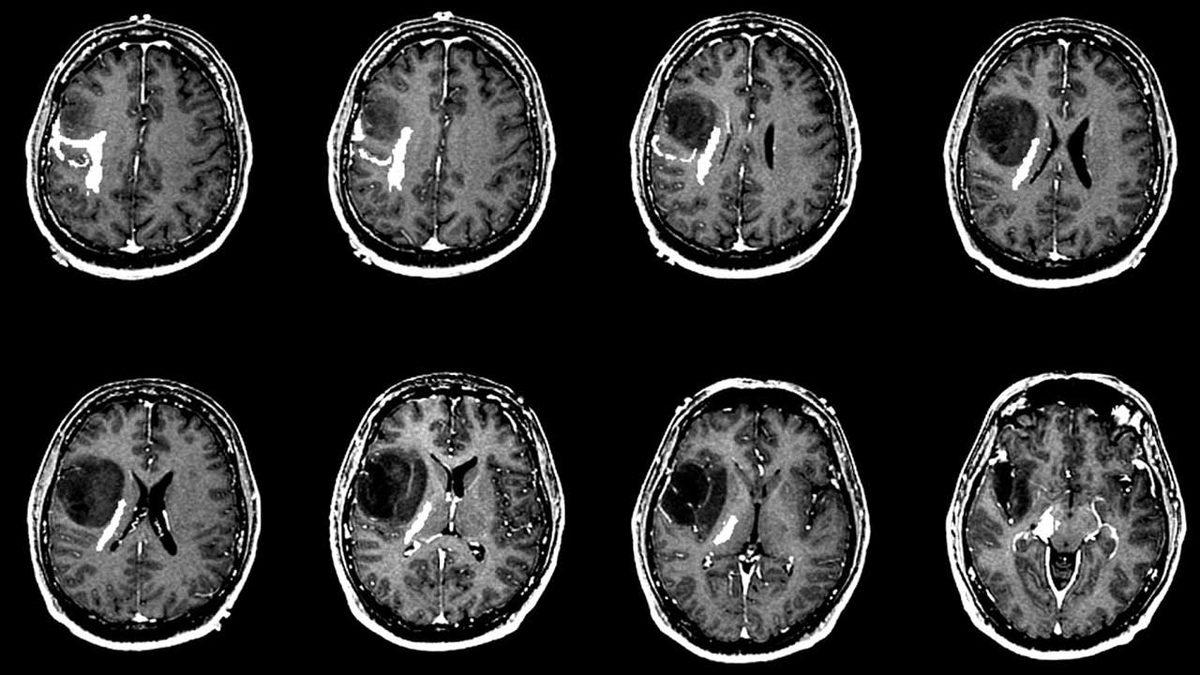

Beynin işlevsel açıdan önemli bölgelerine yakın olan tümörleri çıkarmak için uygulanan bu devrim niteliğinde prosedürde, konuşma ve hareket etmemizi sağlayan beyin dokularının korunması hedef alınıyor. Üstelik bu işlevleri ameliyat sırasında test etmek, tıpta cesur bir adım olarak kabul ediliyor.

Beyin ameliyatı denilince aklınıza tüm çeşitleri gelmesin. Uyanık beyin ameliyatının tercih edildiği bazı özel durumlar var. Bu durumlar ise beyin tümörünün olduğu yerle alakalı. Eğer tümör; beyinde kolları, bacakları ve konuşmayı kontrol eden kısımlara yakınsa cerrah, bu uygulamayı gerekli görerek hastaya öneriyor.

Tümörün; görme, konuşma ve hareket kontrolü sağlayan bölgelerine yakınlığı için beyin haritalaması yapılıyor. Tümörü çıkarırken, haritalama sayesinde kritik bölgelerden kaçınılıyor. Sinirlerin haritasını çıkarmak için kullanılan bu yöntem, ameliyat sırasında hemen geri bildirim almanın tek yolu olarak kabul ediliyor.